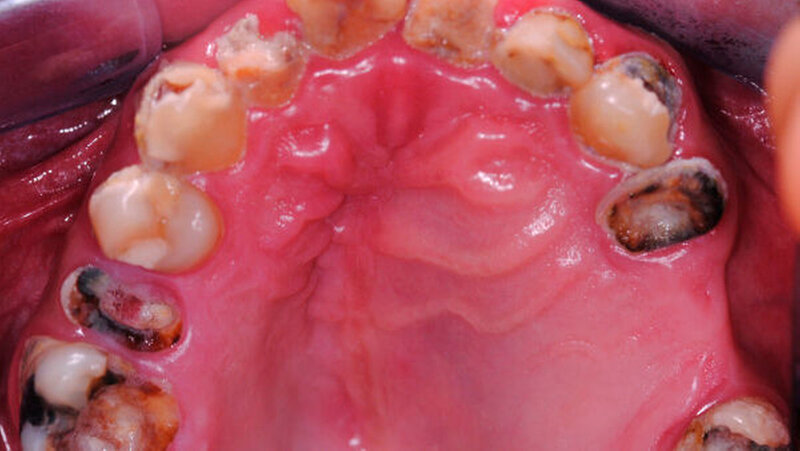

Der intraorale Zahnstatus beschreibt einen insgesamt sanierungsbedürftigen Zustand mit diversen nicht erhaltungswürdigen Zähnen im Unter- und Oberkiefer. Der Oberkiefer zeigte klinisch im zweiten Quadranten eine ausgeprägte palatinale Schwellung (Abbildung 2). Die Panoramaschichtaufnahme bestätigte den klinischen Verdacht auf eine ausgedehnte osteolytische Raumforderung im Oberkiefer. Diese erstreckte sich vom linken Oberkiefer die Mittellinie überschreitend, die gesamte linke Kieferhöhle einnehmend bis zur Regio 14 gehend (Abbildung 3). Durch den Hauszahnarzt konnte ein sechs Jahre zuvor erstellter Zahnfilm zur weiteren Diagnostik hinzugezogen werden.